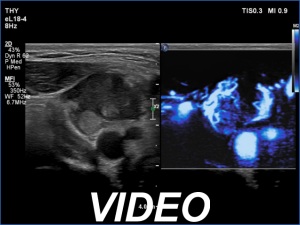

Ultrasonography. The thyroid was hypoechoic. The right lobe had a heterogeneous, dominantly minimally/moderately hypoechoic nodule in the ventrolateral part which had irregular borders and both perinodular and intranodular vascularity. There was another, hyperechoic star-like lesion in the central part of the right lobe. This lesion presented microcalcifications and was avascular. The left lobe was homogeneously hypoechoic.

According to the palpable mass in the right submandibular area, there was a heterogeneous lesion which has hypoechoic and echonormal parts. The mass had irregular margins and showed vascularity. The distance between the submandibular mass and the thyroid was more than 35 mm.